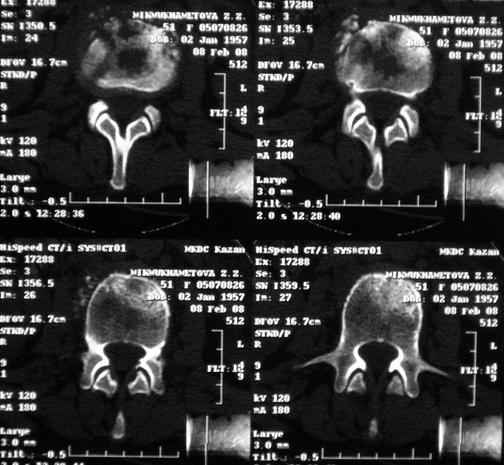

Re: Требуется телеконсультация Вертебролога

послал Коваленко А.Н. 12 Февраль 2008, 22:13

MRI через три недели